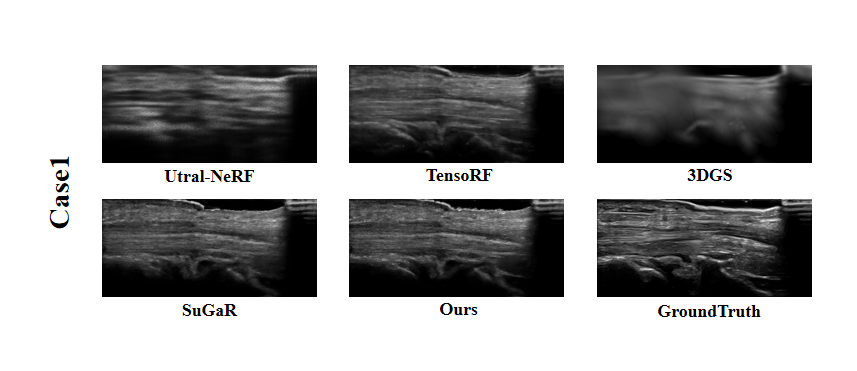

Refer to caption

Figure 6: Visual Comparison for Case 1 in the Clinical Dataset.

From the supplementary experimental results of Fig.6-9 on the Clinical Dataset, UltraGS showed significant advantages in multiple typical cases (Case 1 to Case 6). Compared with other methods [mildenhall2021nerf, chen2022tensorf, wysocki2024ultra, kerbl20233d, guedon2024sugar], UltraGS has achieved better results in the restoration of boundary details, preservation of tissue structure, and clarity of overall reconstruction, demonstrating its robustness and generalization ability in processing complex clinical data. These results fully validate the adaptability of our method in real clinical environments, especially in the face of poor image quality or blurry structural features, UltraGS can still accurately capture key structural information and achieve stable and high-quality novel view synthesis.